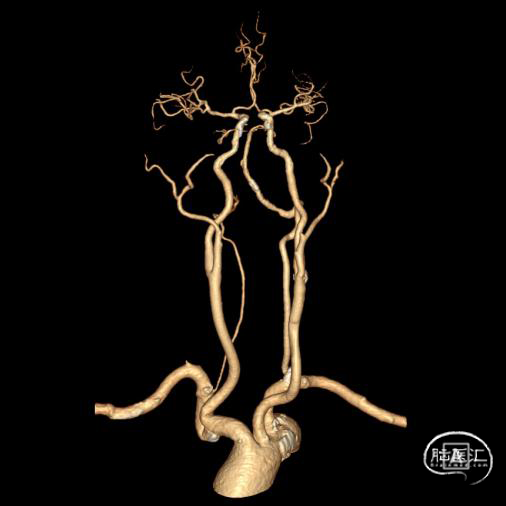

➢头颈部CTA(三维重建MIP像)

➢头颈部CTA(原始像)

该患者术前影像学提示右椎纤细、V4段未汇入基底动脉,考虑孤立椎。且左椎开口存在重度狭窄,左椎V4存在局部重度狭窄可能,故该患者存在血管内介入治疗指征,排除禁忌症后拟行“全脑血管造影术+左侧椎动脉开口血管成形术”。

术前影像考虑右侧孤立椎,左侧椎动脉V1段重度狭窄、狭窄段以远扭曲成襻且合并长节段多发动脉粥样硬化狭窄改变(夹层待排),同时左椎V4段局部重度狭窄可能;

术中造影证实右椎纤细、右椎V4段可见微弱血流入基底动脉、左椎动脉开口闭塞、颈升动脉通过侧支循环向左椎V3供血并逆流至V1中段、左椎V4轻度狭窄;